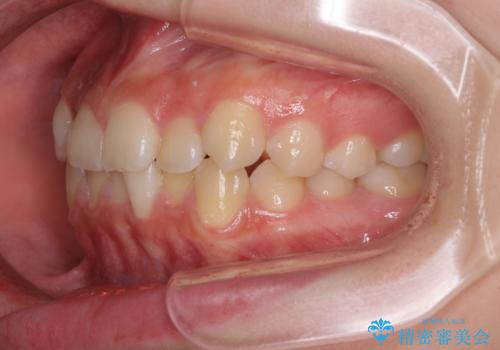

前歯のクロスバイト メタル装置での矯正治療

- 前歯のクロスバイトを気にして来院された患者様です。

前歯の叢生を解消するスペースを獲得するために上顎左右の親知らずを抜歯し、メタルブラケットにて矯正治療を行うこととしました。

当初は1年半程度の治療期間を想定していましたが、上下の正中を合わせていく過程で奥歯の咬みにくさが続いてしまい、2年以上の治療期間を要することとなりました。